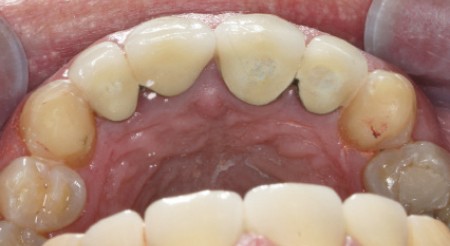

Bruxisme : net avec attrition antérieure marquée en particulier en regard des coiffes céramiques.

Occlusion : décentrage gauche, création d’une légère béance antérieure probable conséquence

de l’atteinte de l’ATM gauche.

Indication de prise en charge du bruxisme du fait de l’ATM fragile, contact avec médecin traitant à propos de l’arthrite dégénérative, pas de gouttière initiale.

Renforcement de la PECC par des collages en composite sur 13 et 23, Réévaluation sur 12 mois…